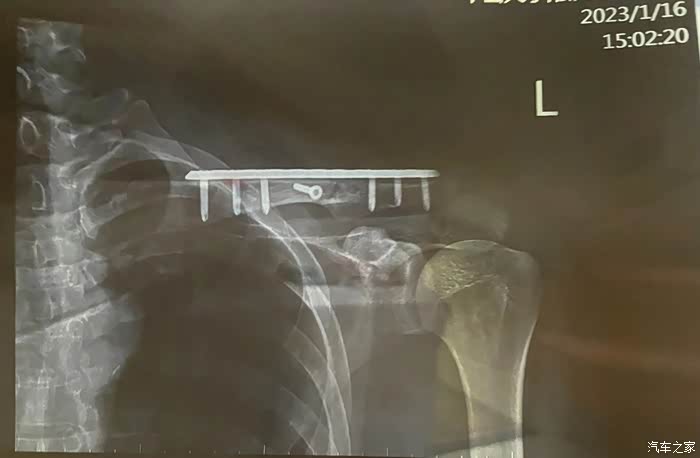

结论,锁骨粉碎性螺旋状骨折,肋骨6-10节五根骨折。双眼视力模糊下降。老人基本没事,除了视力有点下降之外,并且有些轻微的肌肉挫伤。